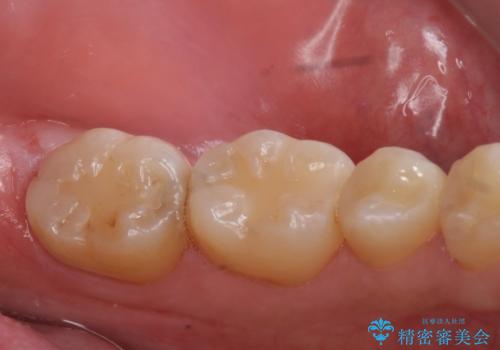

e-maxインレーによる治療

- 定期検診で来院してレントゲンを撮ったところ

歯と歯の間にう蝕ができていました。

拡大鏡下でう蝕を全て除去してe-maxインレーにて治療を行いました。